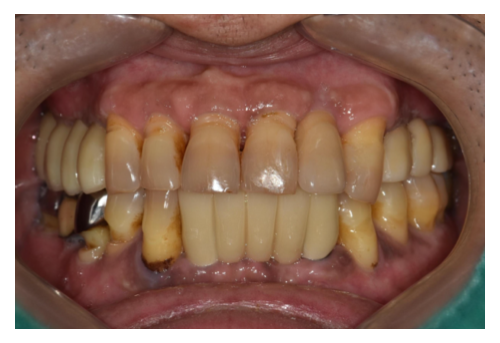

4 50대 남환 임플란트

• 정기적인 치아관리가 되지 않고 왼쪽 어금니가 없는채로 장기간 방치되어 잇몸뼈..